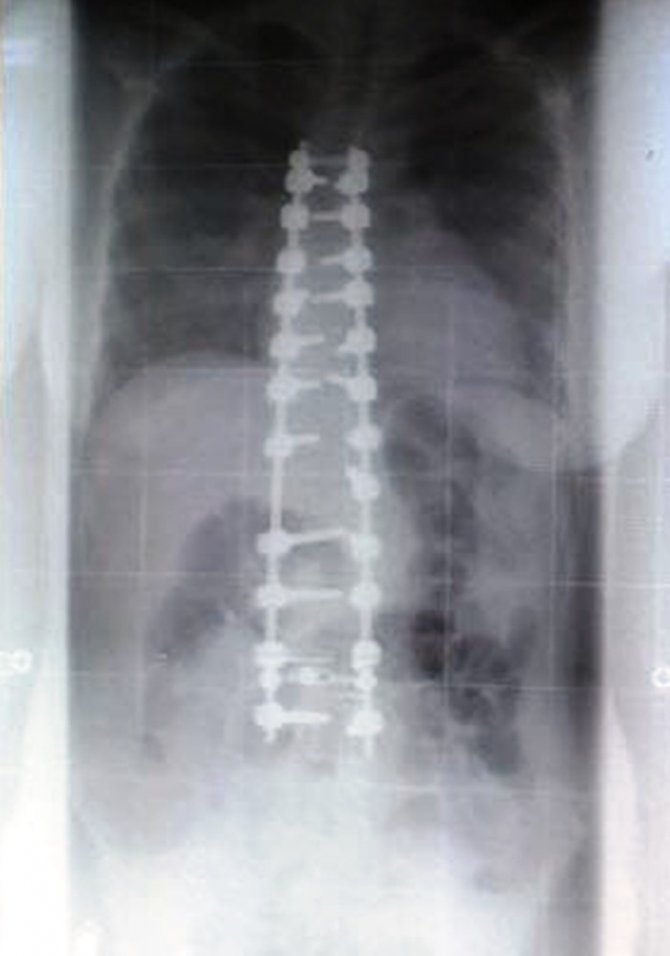

Medikal Park Karadeniz Hastanesinde Ortopedi ve Travmatoloji uzmanı Prof Dr. Çetin Önder, skolyoz cerrahisindeki amacın eğilmiş omurları düzgün bir şekilde dizip birbirine kaynatarak, kaynama sonrasında bu bölge tek bir kemik gibi hareket etmek olduğunu söyledi.

Günümüz teknolojisi skolyoz cerrahlarının eğrilikleri düzeltebilme yeteneklerini artığını söyleyen Önder, "Böylece estetik olarak düzgün bir görüntü elde edilebilir. Eğrilmiş omurların birbirine kaynatıldığı füzyon ameliyatı skolyoz eğriliğinin artmasını engellemekte çok başarılıdır. Omurlar omuriliği korumakla da görevlidirler. Dolayısıyla ameliyat sırasında omuriliğe zarar vermemek için güvenli kalınabilen maksimum düzeltmeyi elde etmeye çalışırlar. Ameliyat kararını deneyimli bir omurga cerrahı ile görüşüldükten sonra ameliyata almak en doğrusudur" diye konuştu.